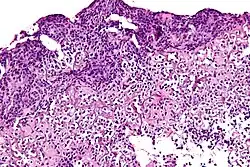

Lepromatous leprosy | Skin biopsy showing epidermal atrophy and multiple dermal infiltrates. | Category: Histopathology of leprosy | Leprosy |

![]() |

Tuberculoid leprosy | Skin biopsy showing multiple peri-appendageal granulomas. | Category: Histopathology of leprosy | Leprosy |